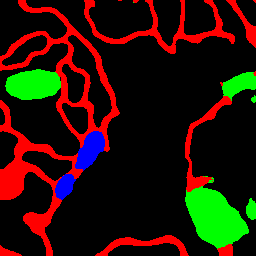

Figure 5: Segmentation result on WBC dataset

We use U-Net [28] as a baseline, which has been widely applied in medical and biological images. Following methods are the comparison methods. two adversarial training methods; pix2pix [15] based on U-Net with a discriminator and Self-Attention GAN (SAGAN) [43] which adds Self-Attention [36] to the discriminator of pix2pix. We also evaluate attention U-Net [23] introduced an attention mechanism called sSE-Block [29] to Skip Connection of U-Net. PDA-Module [21] is a method that applies a bottom-up attention mechanism based on difficulty to U-Net.

Table 2 shows the IoU accuracy on the WBC dataset, and Table 2 shows the experimental results of evaluating WBC dataset with Precision and Recall. Bold red letters in Table represent the best accuracy, and blue and green bold letters are the second and third best. We see that the accuracy of AML-Net is better than that of conventional methods based on U-Net. In particular, we confirm that the accuracies of Top-Down PDA-Module and AML-Net were improved in almost classes compared to pix2pix and SAGAN, which are adversarial training methods without leakage. Especially, in cytoplasm which is the most difficult, large accuracy improvement was observed. In addition, the accuracy of AML-Net was better than other conventional methods in terms of the mean and standard deviation. This indicates that the accuracy of AML-Net is stable and does not depend on the combination of datasets or initial values. In addition, we confirm that the mean IoU of AML-Net based on U-Net is higher than that of Deeplabv3+ [3] and FastFCN [40] based on ResNet-50 [8]. By avoiding the use of very deep networks such as ResNet-50, the training and inference speed can be accelerated, which is an advantage for cell biologists in practical use. From Table 2, we can see that AML-Net has the best Recall for cytoplasm and cell nucleus, and Precision also shows high accuracy. Conventional methods only have high precision or high recall, but AML-Net has an advantage in the balance of precision and recall.

Figure 5 shows segmentation results. We see that the most of conventional methods in the upper image group over-detect the cytoplasm because the color of red blood cells and cytoplasm are similar. In addition, in the lower image group, we can see that the cytoplasm staining is darker and therefore closer to the color of the cell nucleus, and that segmentation is not working well with many conventional methods. Our AML-Net can accurately segment the regions even for images with very similar colors.